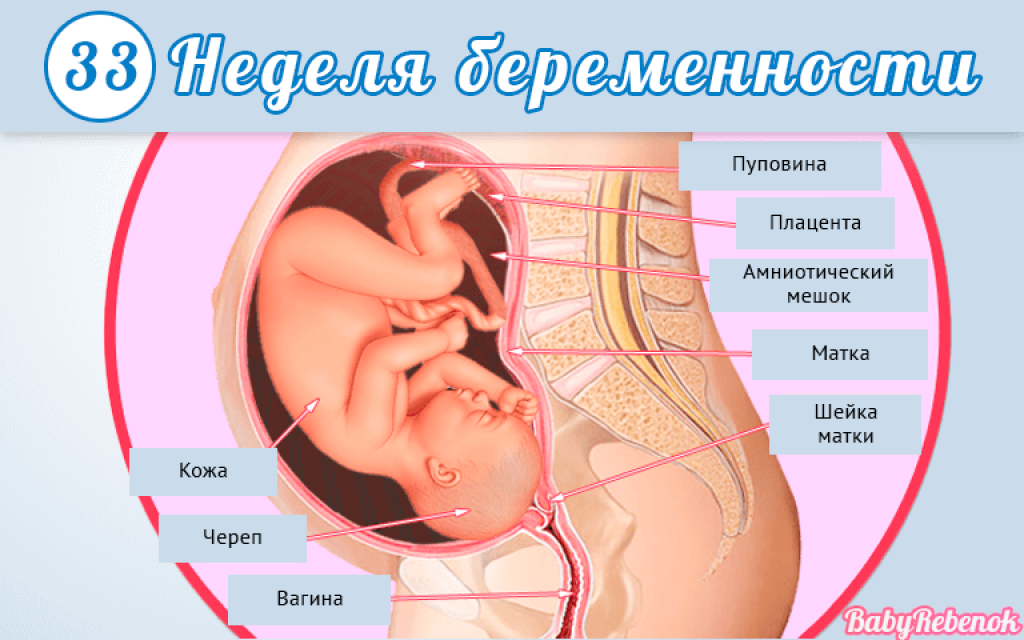

25 недель беременности: Как выглядит будущий малыш

Раздел: Образы вокруг